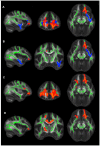

Alzheimeŕs disease (AD) represents the most prevalent neurodegenerative disorder that causes cognitive decline in old age. In its early stages, AD is associated with microstructural abnormalities in white matter (WM). In the current study, multiple indices of diffusion tensor imaging (DTI) and brain volumetric measurements were employed to comprehensively investigate the landscape of AD pathology. The sample comprised 58 individuals including cognitively normal subjects (controls), amnestic mild cognitive impairment (MCI) and AD patients. Relative to controls, both MCI and AD subjects showed widespread changes of anisotropic fraction (FA) in the corpus callosum, cingulate and uncinate fasciculus. Mean diffusivity and radial changes were also observed in AD patients in comparison with controls. After controlling for the gray matter atrophy the number of regions of significantly lower FA in AD patients relative to controls was decreased; nonetheless, unique areas of microstructural damage remained, e.g., the corpus callosum and uncinate fasciculus. Despite sample size limitations, the current results suggest that a combination of secondary and primary degeneration occurrs in MCI and AD, although the secondary degeneration appears to have a more critical role during the stages of disease involving dementia.